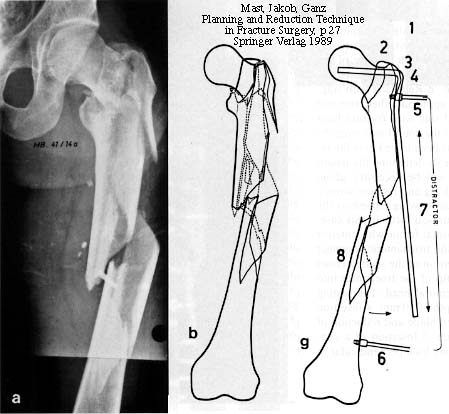

Preop

53 wks

Fx

Nail

It has transverse locking screw holes every 2 cm and oblique screw holes at thetop for neck fixation and so it is like a big intramedullary plate. The externaltargeting jig for the screw holes was very rigid and I was able to interlock in aclosed manner. The only problem is that it was a straight, large diameter (12.5mm) device which could comminute a proximal femur (which has already been done inthis case). The other problem was that it was uncannulated so getting it acrossthe various fractures closed without a guide wire can be tricky.

At any rate, if a device like this is available to you, it may be worthconsidering. After a provisional cerclage/reduction of the proximal femoralshaft, you could get good fixation on at least the proximal medial cortex withmultiple locking screws. You could get perhaps 2 screws into the headneck-fragment through the nail and maybe one or two lag screws or Knowles pinsaround the nail.

If there is delayed union of the neck after the shaft heals, I would remove thenail and do a valgus intertrochanteric osteotomy with a dynamic compression screwor angled blade plate as described in the references below.